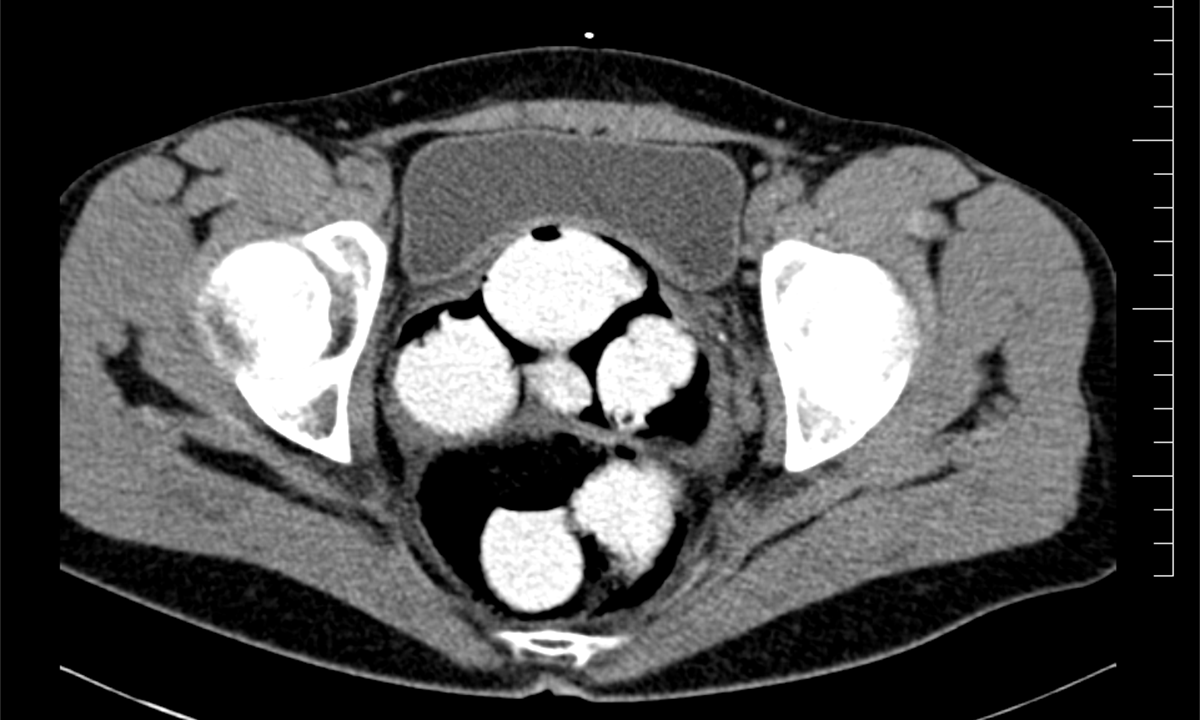

Ke kontrole byl polykač celníky vytipován na základě provedené rizikové analýzy daného letu. Prvotní podezření na pašování drog celníkům potvrdily kontrolní stěry DrugWipe z rukou pašeráka s pozitivní reakcí. Při důkladné kontrole jeho zavazadel a osobní prohlídce nebyly drogy nalezeny, proto bylo provedeno následné CT vyšetření v nemocničním zařízení, které podezření potvrdilo.

Postupně z těla pašeráka vyšlo 124 kontejnerků naplněných bílým práškem. Chemická látka při provedení detekční zkoušky NARK II pozitivně reagovala jako kokain. Celková hmotnost všech kapslí je 1 429,1 g. Určení vlastní hmotnosti a druhu zajištěné drogy je předmětem další odborné expertízy. Podle zkušeností celníků se s největší pravděpodobností jedná o velmi koncentrovaný kokain. Zda byla droga určena na český trh nebo k distribuci v jiné zemi, je předmětem dalšího šetření.